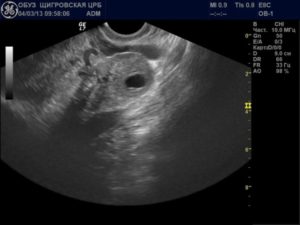

На ранних сроках, когда еще невозможно распознать на УЗИ наличие эмбриона в матке, по характерному для этого этапа беременности увеличению эндометрия можно сделать вывод о зародившейся новой жизни.

Так как в этот период внутренняя оболочка матки выполняет функции еще не сформировавшейся плаценты, то отклонения в толщине в любую сторону, замеченные на УЗИ, необходимо корректировать с помощью терапии, прописанной гинекологом. В противном случае это может помешать вынашиванию малыша.

Размер эндометрия при беременности на ранних сроках является показателем того, насколько правильно происходит этот процесс, и нет ли патологических отклонений. На первых неделях плодное яйцо нельзя выявить на УЗИ, а также отсутствует возможность прослушать сердцебиение ребенка, при беременности толщина эндометрия определяет, произошло ли прикрепление эмбриона.